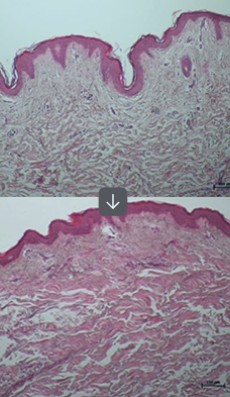

ONDA通过超短微波能量深入真皮层,

促进肌肤弹性提升与胶原活化。

通过高能热量的集中传导,刺激胶原再生并紧致肌肤,

超短微波疗程

同时作用于真皮层的胶原蛋白与脂肪细胞,

帮助提升紧致与改善面部轮廓。